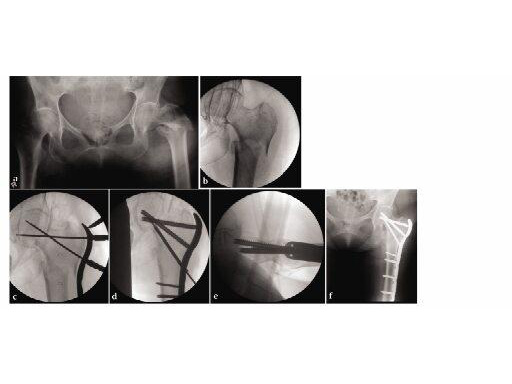

78-year-old osteoporotic female with a left subtrochanteric femur fracture. The proximal femur has a frontal plane fracture in it. Advantages include excellent purchase of the osteoporotic proximal segement, avoidance of abductor devitaliation, and reestablishment of the normal neck-shaft angle.

The LCP Proximal Femur 4.5 is part of the Locking Periarticular Plating System, which merges locking head screw (LHS) technology with conventional plating techniques. It is indicated for pertrochanteric fractures, subtrochanteric fractures, instable intertrochanteric fractures, and intertrochanteric fractures with reverse obliques, as well as malunions and nonunions of these fracture types. The LCP Proximal Femur 4.5 is a stainless steel plate with a limited contact profile. The proximal portion of the plate is anatomically contoured to approximate the lateral profile of the proximal femur. Therefore, it comes in a right and left version. The two proximal screw holes accept 7.3 mm cannulated locking and 7.3 mm cannulated conical screws. The third locking hole accepts a 5.0 mm cannulated LHS and is angled to converge at the tip of the proximal 7.3 mm screw and is intended to resist varus deformity forces. The remaining screw holes are locking compression plate (LCP) holes which combine a dynamic compression unit (DCU) hole with a locking hole. This provides the surgeon with the flexibility to gain axial compression and angular stability throughout the length of the plate. Because of the proximal screw configuration, the plate can be compressed with the articulated tension device to create a load sharing construct. This is important and should be the aim whenever possible. This plate can be secured to osteopenic bone, or to bone where there is a cortical defect. The LCP Proximal Femur 4.5 uses existing screws and instrumentation. The stainless steel screws necessary for implantation are: 7.3 mm cannulated conical, 7.3 mm cannulated locking head, 5.0 mm cannulated conical, 5.0 mm cannulated locking head, 5.0 mm and 4.0 mm StarDrive locking head screws, and 4.5 mm cortex screws.